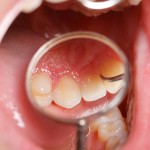

Reverse Gum Disease and Heart Disease with Vitamin C

Did You Know...

... that you can help reverse gum disease and its associated risk of heart disease naturally, using just a vitamin?

Typically, when we...